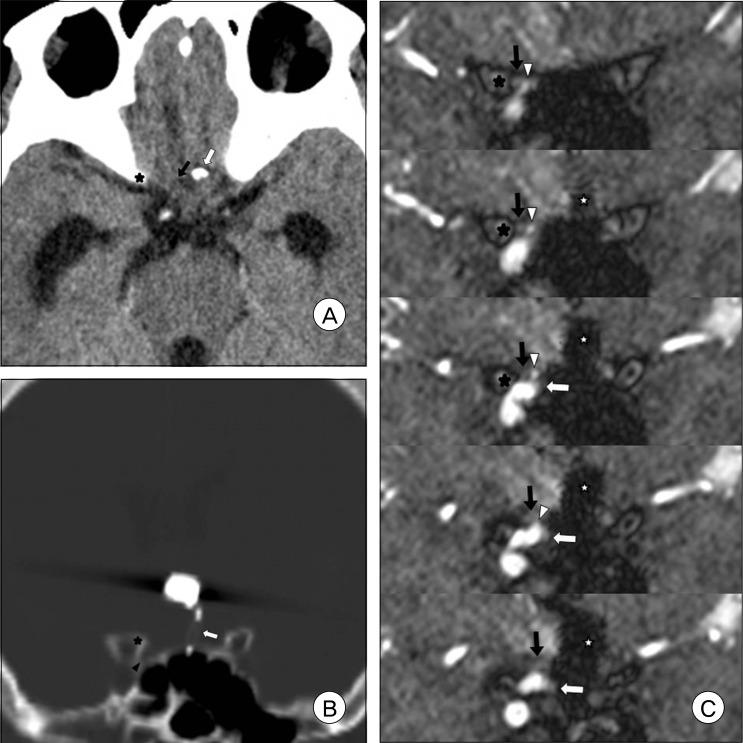

Infraoptic anterior cerebral artery (ACA) is an extremely rare congenital anomaly. This anomalous artery usually arises from the intradural internal carotid artery (ICA) near the level of the ophthalmic artery (OA) or rarely from the extradural ICA. This anomaly frequently harbors a cerebral aneurysm, and may involve other coexisting vascular anomalies. In the case of this anomaly, surgical treatment of the aneurysm at the proximal ACA or anterior communicating artery (ACoA) may sometimes be difficult, because the veiled proximal ACA by the optic nerve would make proximal control inconvenient and the vertical midline segment of the proximal ACA would frequently form a superiorly directing aneurysm with a relatively high position. We report on an extremely rare case of a ruptured aneurysm at the infraoptic azygous ACA, possibly having an extradural origin, accompanied by contralateral ICA agenesis, and also introduce a feasible method for treatment by Y-stent assisted coil embolization.

视交叉下大脑前动脉(ACA)是一种极其罕见的先天性异常。这种异常动脉通常起源于硬脑膜内颈内动脉(ICA)靠近眼动脉(OA)水平处,或很少起源于硬脑膜外ICA。这种异常常伴有脑动脉瘤,且可能合并其他并存的血管异常。对于这种异常情况,在ACA近端或前交通动脉(ACoA)处进行动脉瘤的手术治疗有时可能会很困难,因为视神经遮挡了ACA近端会使近端控制不便,且ACA近端的垂直中线段常形成位置相对较高的向上指向的动脉瘤。我们报告了一例极其罕见的视交叉下奇异性ACA动脉瘤破裂病例,可能起源于硬脑膜外,伴有对侧ICA缺如,并介绍了一种通过Y型支架辅助弹簧圈栓塞进行治疗的可行方法。